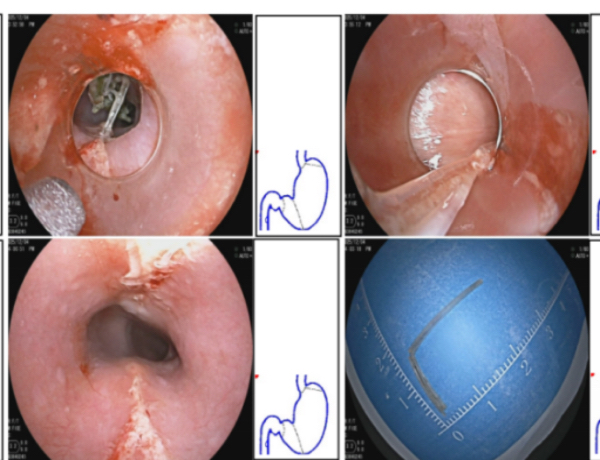

“患者的生命安全永远是第一位的!”面对极高风险,医疗团队没有退缩,迅速制定周密手术方案,从内镜器械选择、术中监测到应急准备,每个环节都经过反复推演。手术当天,在医护团队紧密配合下,梁尔博医生凭借丰富经验,在高清胃镜引导下稳健操作,于狭窄食管内精准定位,成功取出这枚让多家医院望而却步的“致命鱼刺”。术后彭先生迅速恢复,疼痛与呼吸困难症状消失,不久痊愈出院。